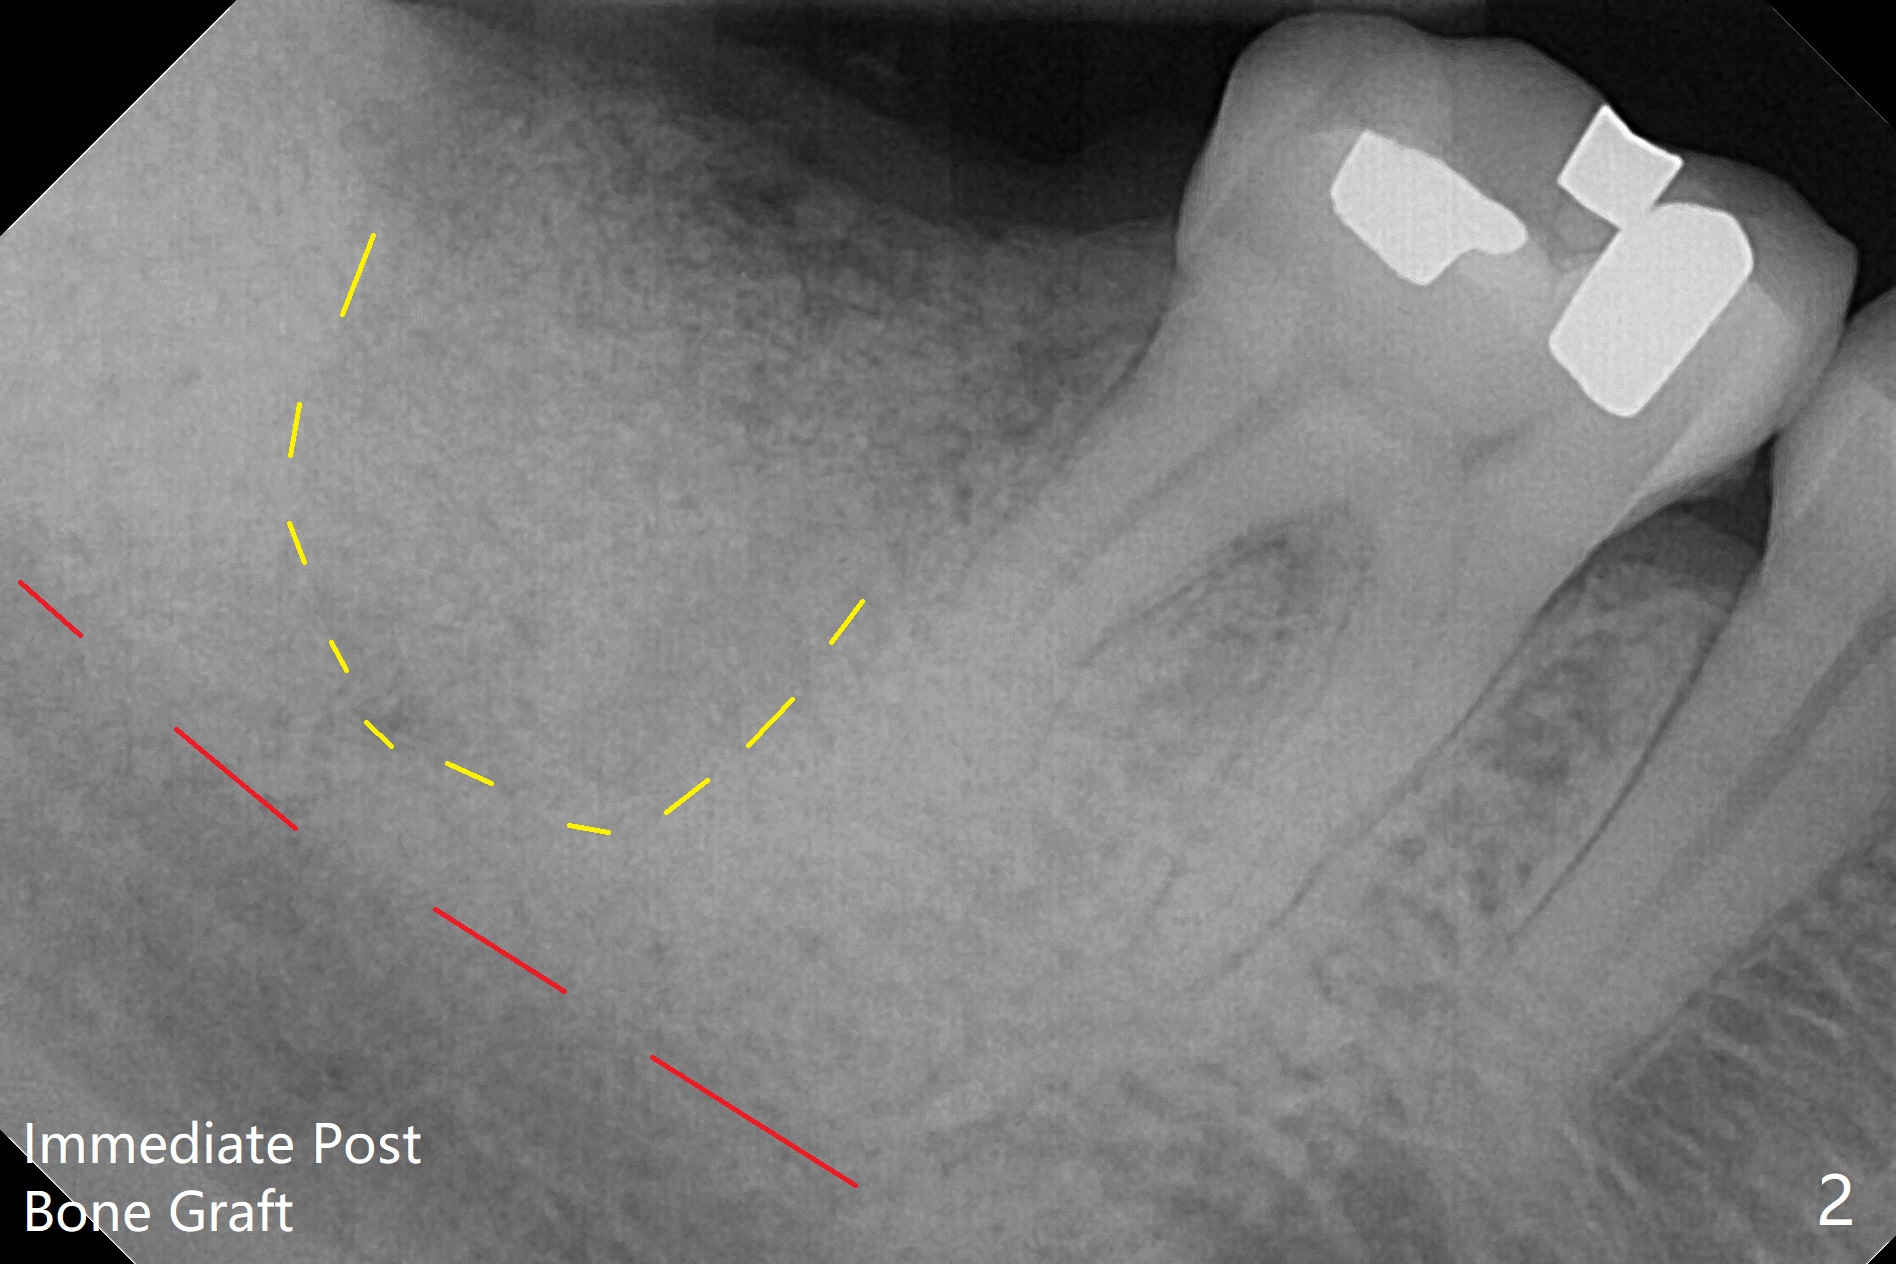

After immediate implant at #3, the tooth #31 with distal root fracture (Fig.1 *) and being close to the Inferior Alveolar Canal (red dashed line) is extracted for socket preservation (Fig.2 yellow dashed line). Although no PRF membrane is used to cover the socket, allograft is mixed with PRF liquid. A piece of 6-month membrane is used instead. The bone density is average 1000 units (Fig.3) and the ridge height is maintained 6 months postop (Fig.4). In fact the bone density of the grafted bone is low as compared to that of the native one.